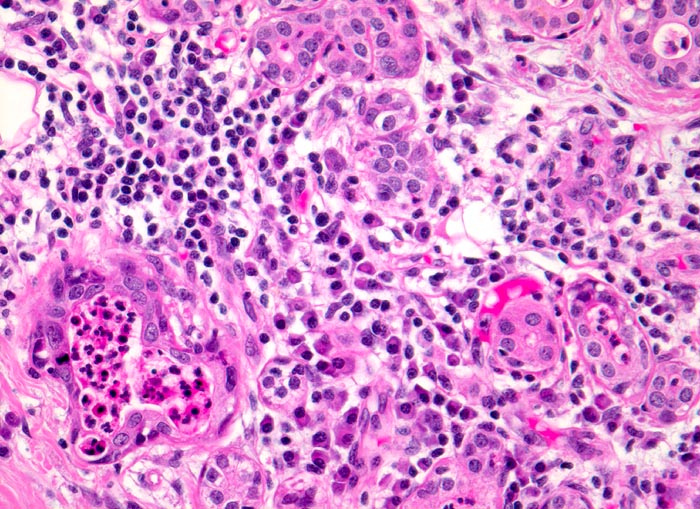

floride chronische Sialadenitis bei Sialolithiasis.

Glandula submandibularis

Drüsenläppchen mit ödematösem lymphoplasmazellulär infiltriertem Stroma. Zwei Drüsenlumina sind leicht erweitert und enthalten Eiter. Die Drüsenazini sind atrophiert.